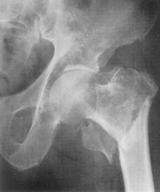

TUBERCULOZA COXO-FEMURALĂ (COXALGIE)

În perioada de stare, capul femural este partial osteolizat, diafiza este subtire, decalcificata, la fel ca si acetabulul.

Spatiul articular este îngustat, contururile osoase sunt sterse, neregulate.

Partile moi sunt mult tumefiate.

În perioada de reparatie se produce anchiloza osoasa cu disparitia totala sau partiala a spatiului articular